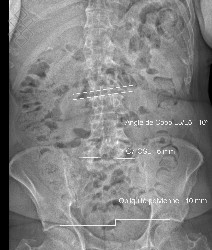

TéléRadiographie du Rachis en totalité